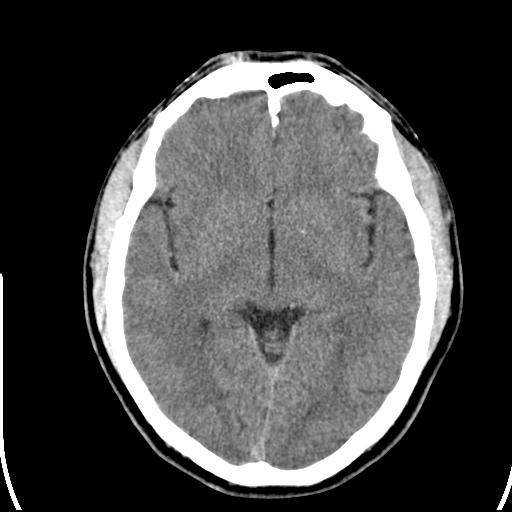

标题: CT25435:头皮下高密度影???

头皮下高密度结节影???临床上在老年男性比较常见。大家看看是什么?成因是? 本例患者,男性,51岁。外伤来诊。无染发史及发根植入史。